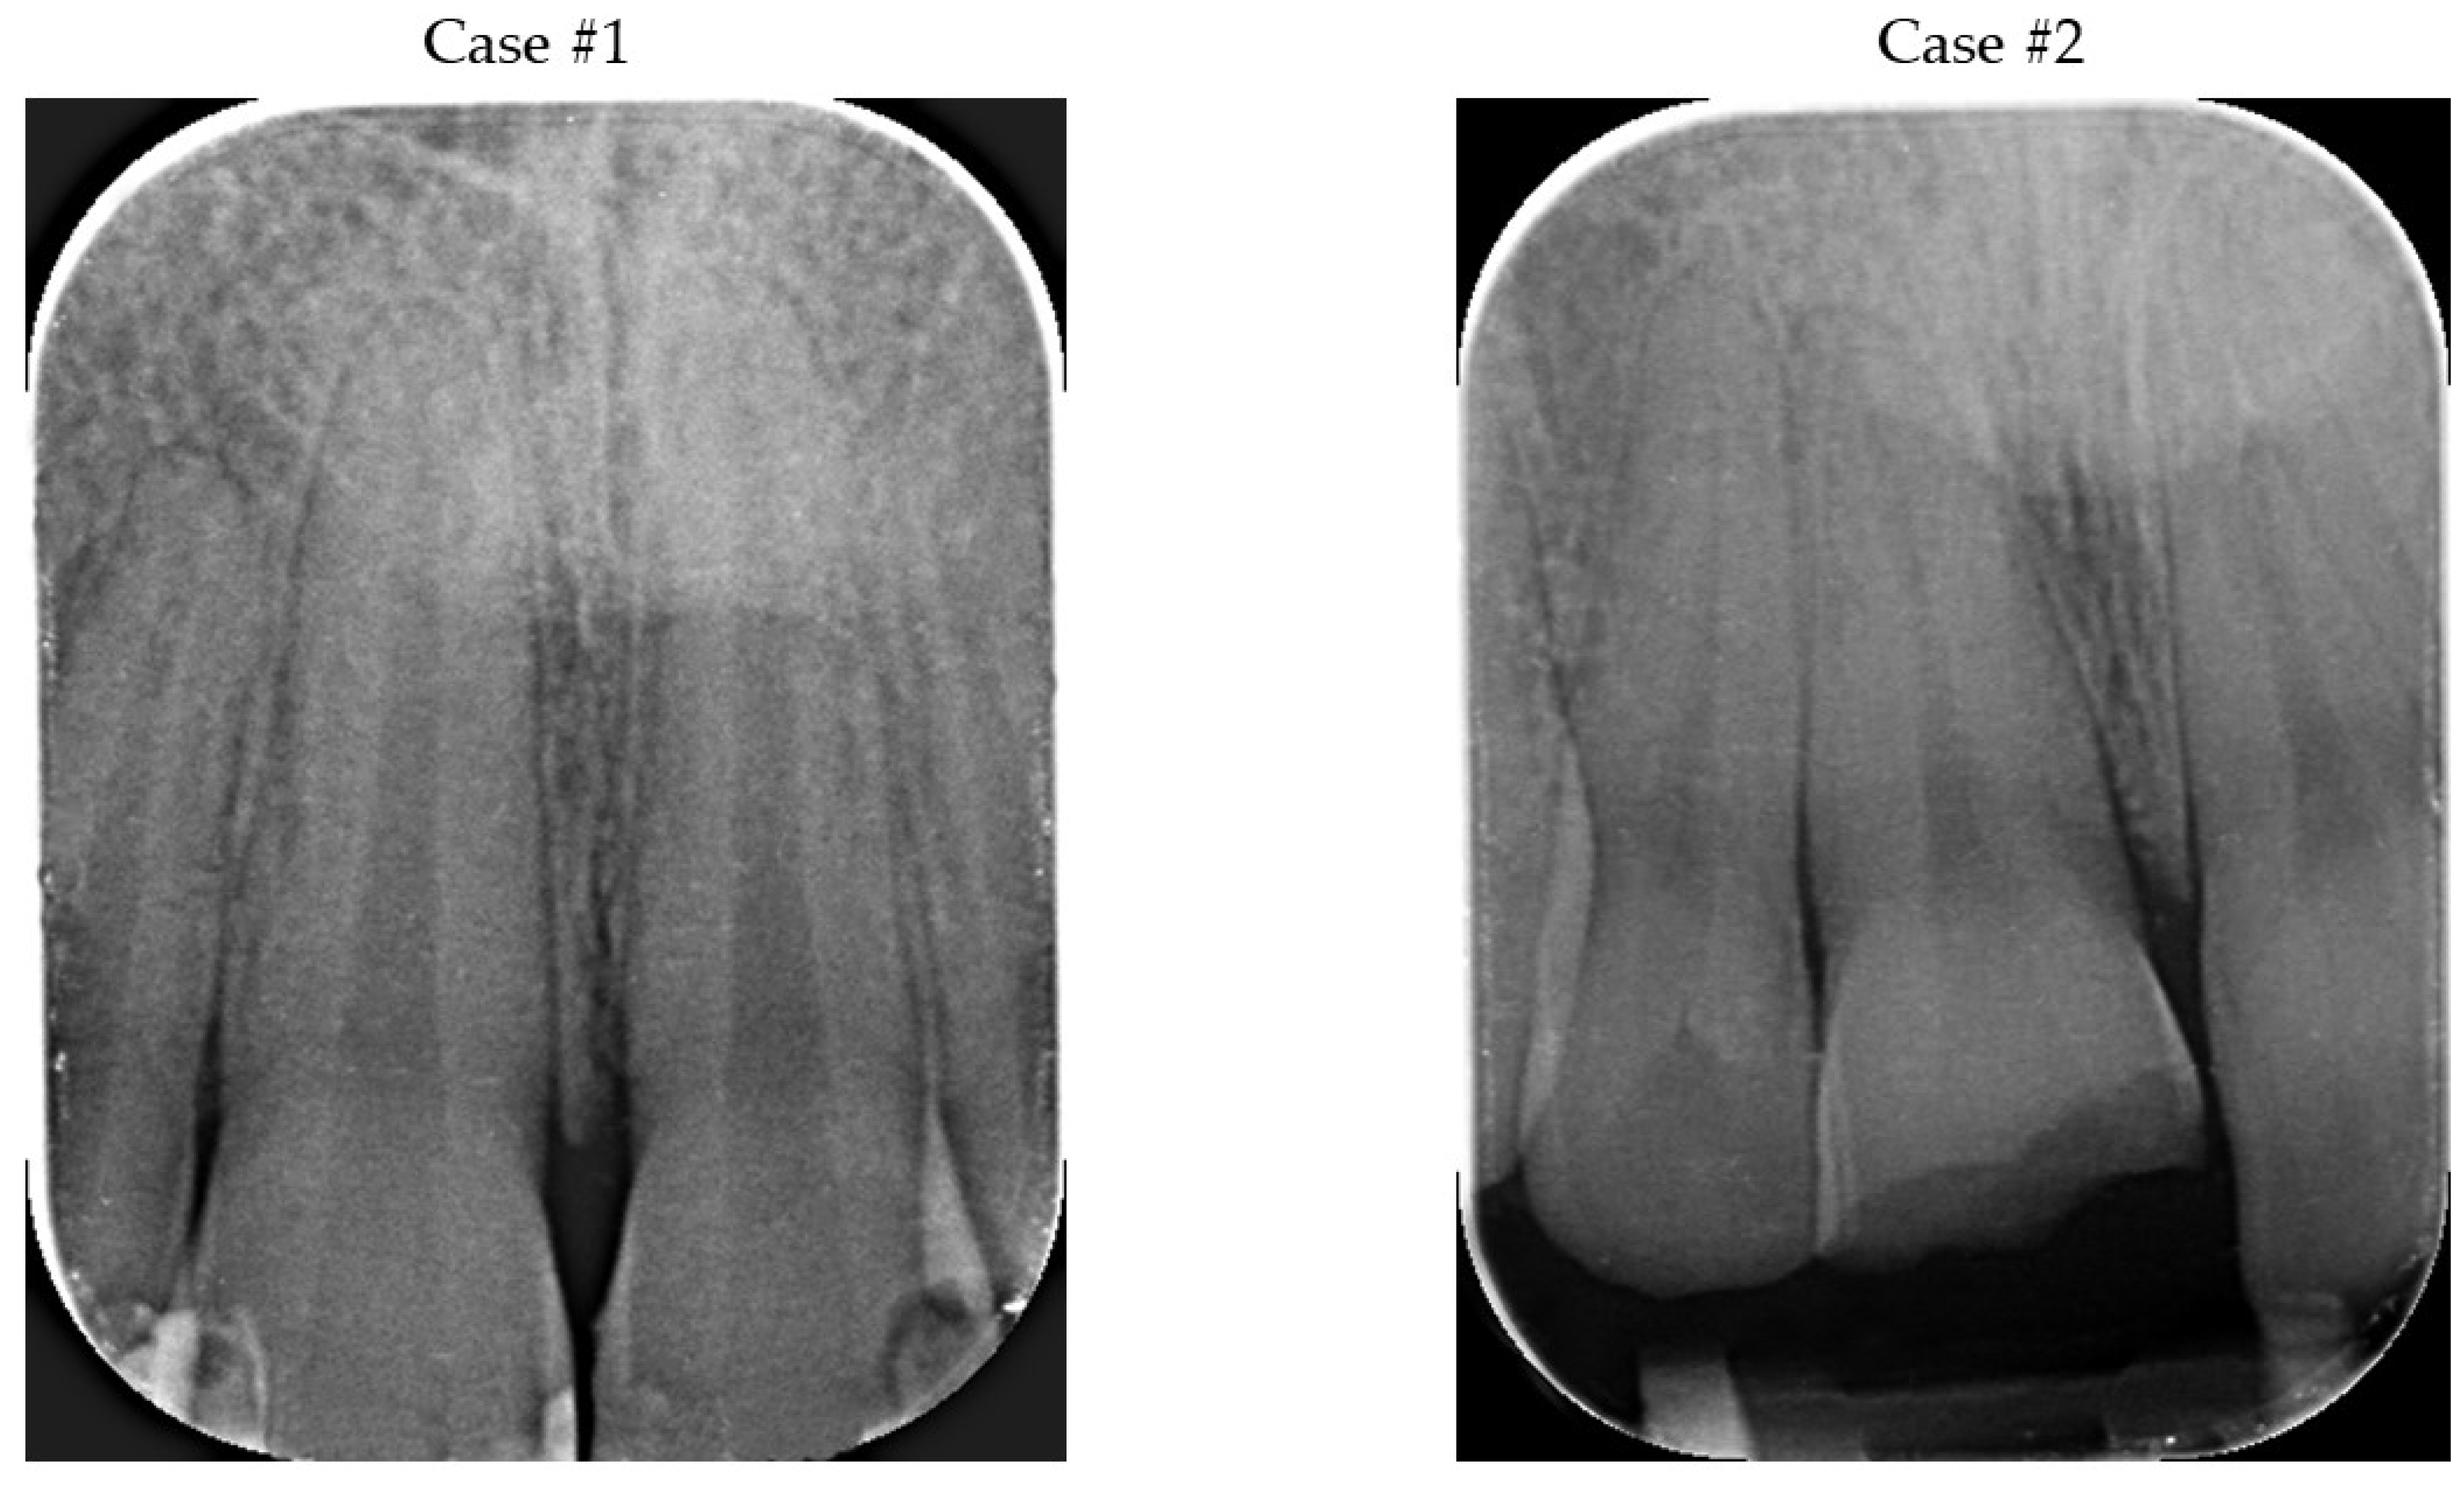

2. Presentation of Cases

2.1. Diagnosis